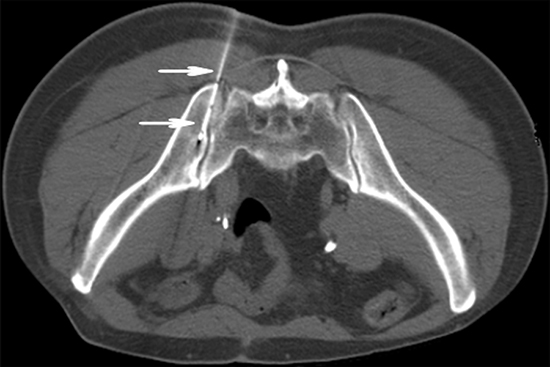

Before 125I brachytherapy, 5mm axial enhanced CT images were obtained in all patients (Figure 1A). Treatment was mapped and dosed for each patient using a computerized treatment planning system (TPS) (RT-RSI, Beijing Atom and High Technique Industries Inc, Beijing, China).

Figure 1: A. Preoperative computed tomography (CT) image was obtained for targeting bone areas of interest, which showed one lesion in right iliac bone (arrowhead). B. Dose volume histograms (DVH). The prescription dose is 120 Gy during the planning. A total of 90% of the tumor target (D90) received 134.4 Gy, and 96.2% of the tumor received 100% of the prescribed dose (V100 = 96.2%). C. Isodose curves plotted by the treatment planning system (TPS), the planning target volume (PTV) edge was covered by isodose curve from 70% to 90%.

A careful delineation of the gross tumor volume (GTV), planned target volume (PTV) and surrounding vital organs (e.g. spinal cord) was sought in every CT slice. PTV is defined as a 1.5 cm of expansion external to the GTV. The prescribed dose was averaged 120 Gy (range 100-140 Gy). Based on three orthogonal diameters within the target tumor and a prescribed matched peripheral dose (MPD) of averaging 120 Gy, TPS generated a dose-volume histogram (DVH), isodose curves of different percentages, and calculated the position of brachytherapy applicator, dose and number of implanted seeds (Figure 1B, 1C). The PTV edge was accounted by the 70%-90% isodose curve. The entry site and path of the needle were determined to avoid vital organs and tissues.